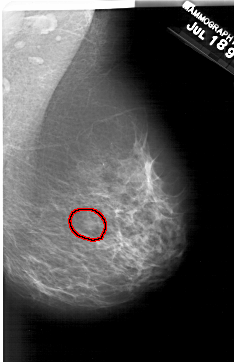

A_2001_1.LEFT_MLO

LEFT_MLO LINES 6196 PIXELS_PER_LINE 3886 BITS_PER_PIXEL 12 RESOLUTION 43.5 NON_OVERLAY

FILE: A_2001_1.RIGHT_CC.OVERLAY

TOTAL_ABNORMALITIES 1

ABNORMALITY 1

LESION_TYPE MASS SHAPE OVAL MARGINS OBSCURED

ASSESSMENT 2

SUBTLETY 3

PATHOLOGY BENIGN

TOTAL_OUTLINES 1

BOUNDARY